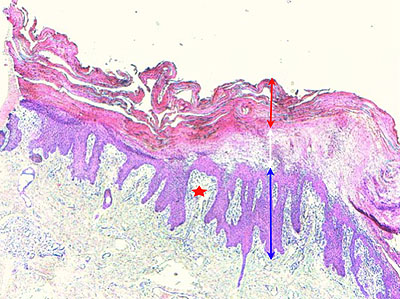

Photo 2 (Hémalun Eosine X 40) : au faible grossissement, l’épiderme revêt un aspect bleu-blanc-rouge,

bleu pour hyperplasie des couches basales, blanc pour vacuolisation des acanthocytes sous-cornés et

rouge pour parakératose de la couche cornée. Le derme est faiblement à modérément inflammatoire.

Légendes de la Photo 2 :

- Flèche bleue : hyperplasie des couches basales

- Flèche blanche : vacuolisation des acanthocytes sous-cornés

- Flèche rouge : pour parakératose de la couche cornée

- Étoile rouge : Le derme est faiblement à modérément inflammatoire